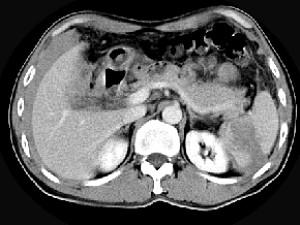

问题 男,55岁,左上中腹部突发性疼痛,CT扫描如图,最可能的诊断是 ( )

选项 A、脾脓肿 B、脾转移瘤 C、脾淋巴瘤 D、脾血管瘤 E、脾肿瘤破裂出血

答案 E